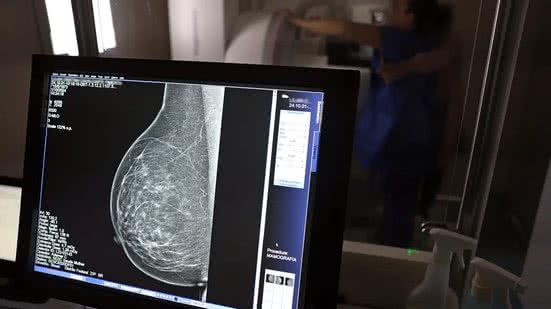

Ministério da Saúde passa a recomendar mamografia a partir dos 40 anos - José Cruz / Agência Brasil

O Ministério da Saúde passou a recomendar o acesso a mamografia, via Sistema Único de Saúde (SUS), para mulheres de 40 a 49 anos – mesmo que não haja sinais ou sintomas de câncer de mama. De acordo com a pasta, a faixa etária concentra 23% dos casos da doença, e a detecção precoce aumenta as chances de cura.

Até então, a orientação era que o exame fosse feito a partir dos 50 anos.